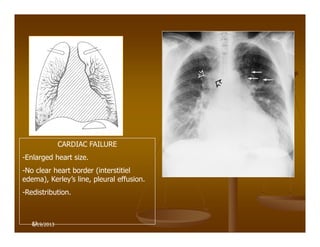

CARDIAC FAILURE

-Enlarged heart size.

-No clear heart border (interstitiel

edema), Kerley’s line, pleural effusion.

-Redistribution.

6/19/2013